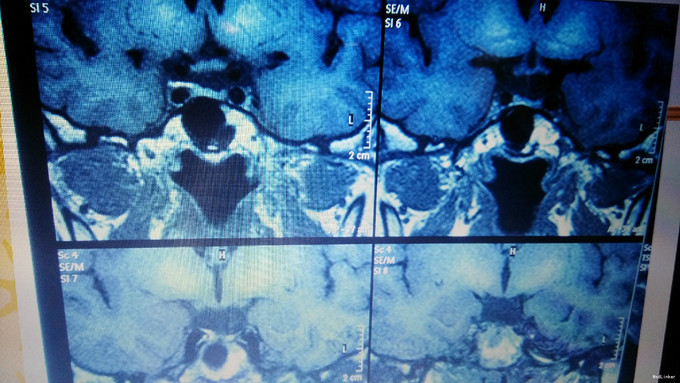

主诉:口渴多饮多尿35年,无月经来潮 现病史:患者6岁时无明显诱因出现口渴,大量饮水,多尿,曾在我院儿科就诊,诊断为“尿崩症”,给予垂体后叶素治疗,症状可好转,但患者未继续复查治疗,饮水量多于正常人每日饮水量。患者青春期时第二性征发育不明显,无月经来潮。20岁时于当地医院就诊,给予“黄体酮”治疗,可出现月经,量少,持续2-3天。患者未坚持服用药物,之后无月经出现。2年前开始多次出现鼻粘膜出血,量不详。患者有头痛、乏力症状,无头晕、视力模糊、无泌乳。

查体:乳房发育幼稚,乳晕浅,毛发稀疏,腋毛、阴毛无,眉毛稀疏。皮肤无瘀斑,眼睑轻度水肿 辅助检查:性腺轴:雌二醇96.50pmol/l,雌三醇<0.24nmol/l,孕酮<0.64nmol/l,FSH 0.92 mIU/ml, LH 0.17mIU/L 甲状腺轴:TSH 3.0433mIU/L, FT4 8.7700pmol/l,FT3 3.8100pmol/l 生长激素:0.20mIU/L,PRL:117.0mIU/L 肾上腺轴: 皮质醇(pg/ml) ACTH(mmol/l) 8:00 112.7 20.48 15:00 57.03 14.40 24:00 50.51 10.71 OGTT-OGIRT-OGCPRT 0分 30分 60分 120分 180分 葡萄糖(mmol/l)4.67 8.96 8.78 4.27 2.18 C肽(pmol/l) 1775.7 2496.9 6616.7 >6660.0 2939.8 胰岛素原(pg/ml)22.53 131.6 >200 198.20 21.03 患者无糖尿病,但存在胰岛素抵抗 ACTH兴奋实验: 12月17日 12月18日 ACTH(mmol/l) 皮质醇(pg/ml) ACTH(mmol/l) 皮质醇(pg/ml) 8:00 114.70 8.67 8:00 84.62 10.92 16:00 58.09 8.61 25单位ACTH泵空静点8小时 16:00 643.70 2000 12月19日 12月20日 ACTH(mmol/l) 皮质醇(pg/ml) ACTH(mmol/l) 皮质醇(pg/ml) 8:00 319.00 22.13 8:00 242.20 25.94 25单位ACTH泵空静点8小时 25单位ACTH泵空静点8小时 16:00 717 2000 16:00 843 2000

诊断:中心性肥胖(中度) 下丘脑综合征伴空泡蝶鞍综合征 治疗:患者垂体前叶功能减退,性腺轴计划给予人工月经治疗。